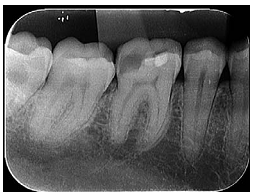

Odontologia » Patologias Endodônticas: Diagnóstico e Tratamento, Endodontia

A radiografia apresentada refere-se ao exame de um paciente de vinte e cinco anos de idade que se queixava de dor espontânea na região inferior direita da face. Na realização do teste térmico de sensibilidade pulpar a frio no dente 46, houve exacerbação da dor.

Nesse caso clínico, o diagnóstico do paciente é de pulpite